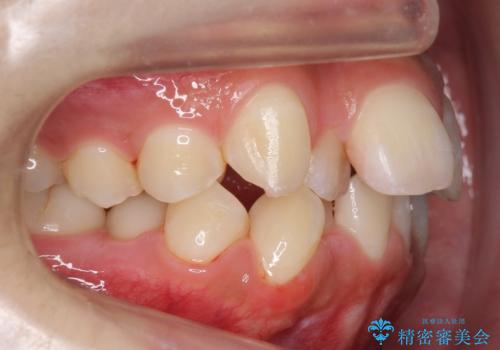

- 前歯のがたつきを主訴に来院。

顔が小さく、顎に大きな歯が入りきらない状態でした。

抜歯してワイヤー矯正を行いました。